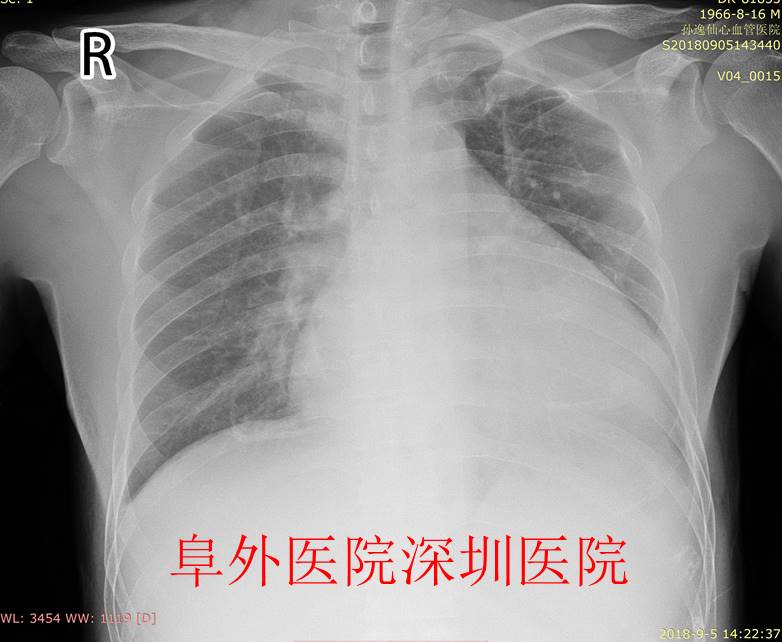

2018年9月中国医学科学院阜外医院深圳医院心律失常科收治了1名长期持续房颤患者,他发生了严重心衰、不能平卧而入院。入心脏彩超提示左室射血分数严重下降(EF10-15%),二尖瓣、三尖瓣出现严重关闭不全,左心房内径(48mm,正常人不超过35mm)、左心室(左室舒张末径57mm,正常人不超过50mm)显著扩大。胸片提示心影巨大,考虑扩张型心肌病可能性大了。药物治疗效果不好,难道只有走心脏移植这条路吗?

图2. 患者术前胸片提示巨大心脏